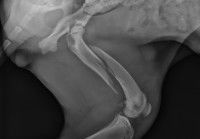

C'est pourquoi, si jamais on soupçonne une fracture, le mieux est de se rendre tout de suite chez son vétérinaire habituel (ou un autre, si celui-ci n'est pas disponible) pour qu'il puisse réaliser un diagnostic précis. Cela passe en général par une radiographie, qui est l'examen le plus approprié pour visualiser l'état des os, repérer un éventuel problème à ce niveau et évaluer l'ampleur des dégâts le cas échéant.

Elle n'est toutefois pas exempte d'inconvénients. En particulier, elle requiert un suivi régulier chez le vétérinaire pour vérifier via des radiographies que les os restent bien positionnés et qu'ils repoussent correctement. Si l'une de ces radiographies semble montrer que la fracture ne guérit pas convenablement (par exemple du fait que les os ne sont pas bien restés en place), il peut être nécessaire de changer le plâtre ou l'attelle afin de rectifier le tir.